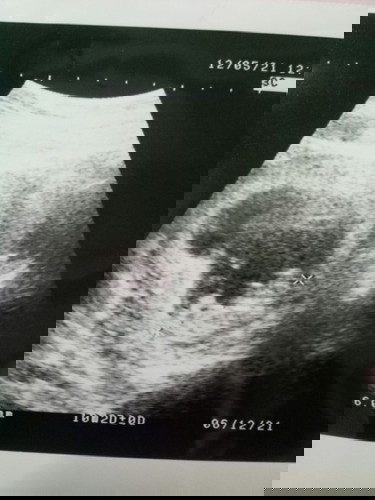

20/10/2021 วันนี้ไปหาหมอมาค่ะหมอซาวต์ดูน้องๆไม่ยอมกลับหัว33w6แล้วแม่คนไหนเจอแบบนี้ไหมค่ะแล้วมี

โอกาสที่จะกลับหัวไหมค่ะแม่บ้านนี้ไปหาหมอให้หมอซาวต์ดูตลอดค่ะซาวต์ทั้งหมด6ครั้ง ครั้งที่,3,4,หมอบอกว่าน้องกลับหัวแล้ว ครั้งที่5พอเข้าเดือนที่7น้องเอาก้นลงตอนนี้ ็อีก5วันก็8เดือนเต็มแล้ว ยังไม่เอาหัวลง แม่นี้เครียดเลยค่ะ#ขอคำแนะนำหน่อยค่ะ #ท้องแรกคะ #ใครมีประสบการณ์